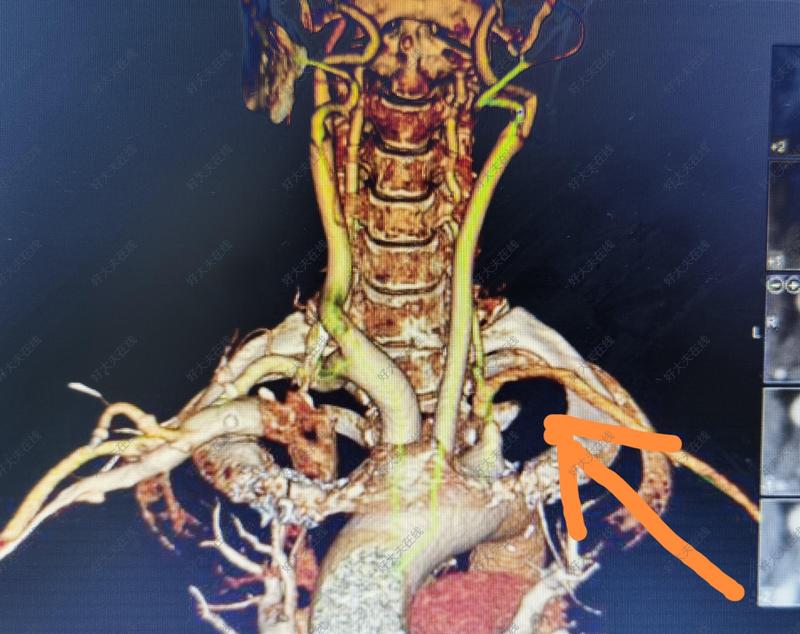

頸動脈重度狹窄合并鎖骨下動脈狹窄,盜血綜合征的同期開通

男性65歲患者,左側(cè)頸動脈重度狹窄,合并左側(cè)鎖骨下動脈閉塞,盜血綜合征,亞急性腦梗塞患者。雙上肢動脈血壓相差60mmHg,左上肢無力,間斷頭暈。全麻下行左側(cè)鎖骨下動脈開通支架植入,左側(cè)頸動脈支架植入。造影顯示,即刻恢復(fù)向腦部的正向血流。手術(shù)順利完成。針對頸動脈狹窄合并鎖骨下動脈狹窄,尤其是盜血綜合征的患者,CAS手術(shù)有優(yōu)勢。